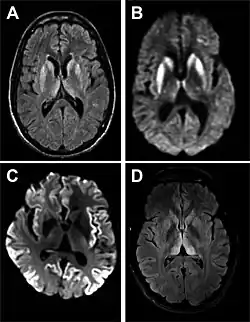

MRI of iCJD because of growth hormone

The defective protein can be transmitted by contaminated harvested human brain products, corneal grafts,[28] dural grafts,[29] or electrode[30] implants and pituitary human growth hormone, which has been replaced by recombinant human growth hormone that poses no such risk.[31]

Imaging of the brain may be performed during medical evaluation, both to rule out other causes and to obtain supportive evidence for diagnosis. Imaging findings are variable in their appearance and also variable in sensitivity and specificity.[49] While imaging plays a lesser role in diagnosis of CJD,[50] characteristic findings on brain MRI in some cases may precede onset of clinical manifestations.[51]

Brain MRI is the most useful imaging modality for changes related to CJD. Of the MRI sequences, diffuse-weighted imaging sequences are most sensitive.[52] Characteristic findings are as follows:

dwMRI, FDG PET and post mortem histology from a patient who presented with sCJD aged 66

• Focal or diffuse diffusion-restriction involving the cerebral cortex or basal ganglia. The most characteristic and striking cortical abnormality has been called "cortical ribboning" or "cortical ribbon sign" due to hyperintensities resembling ribbons appearing in the cortex on MRI.[53] The involvement of the thalamus can be found in sCJD, is even stronger and constant in vCJD.[54]

• Varying degree of symmetric T2 hyperintense signal changes in the basal ganglia (i.e., caudate and putamen), and to a lesser extent globus pallidus and occipital cortex.[50]

Brain FDG PET-CT tends to be markedly abnormal, and is increasingly used in the investigation of dementias.

• Patients with CJD will normally have hypometabolism on FDG PET.[55]